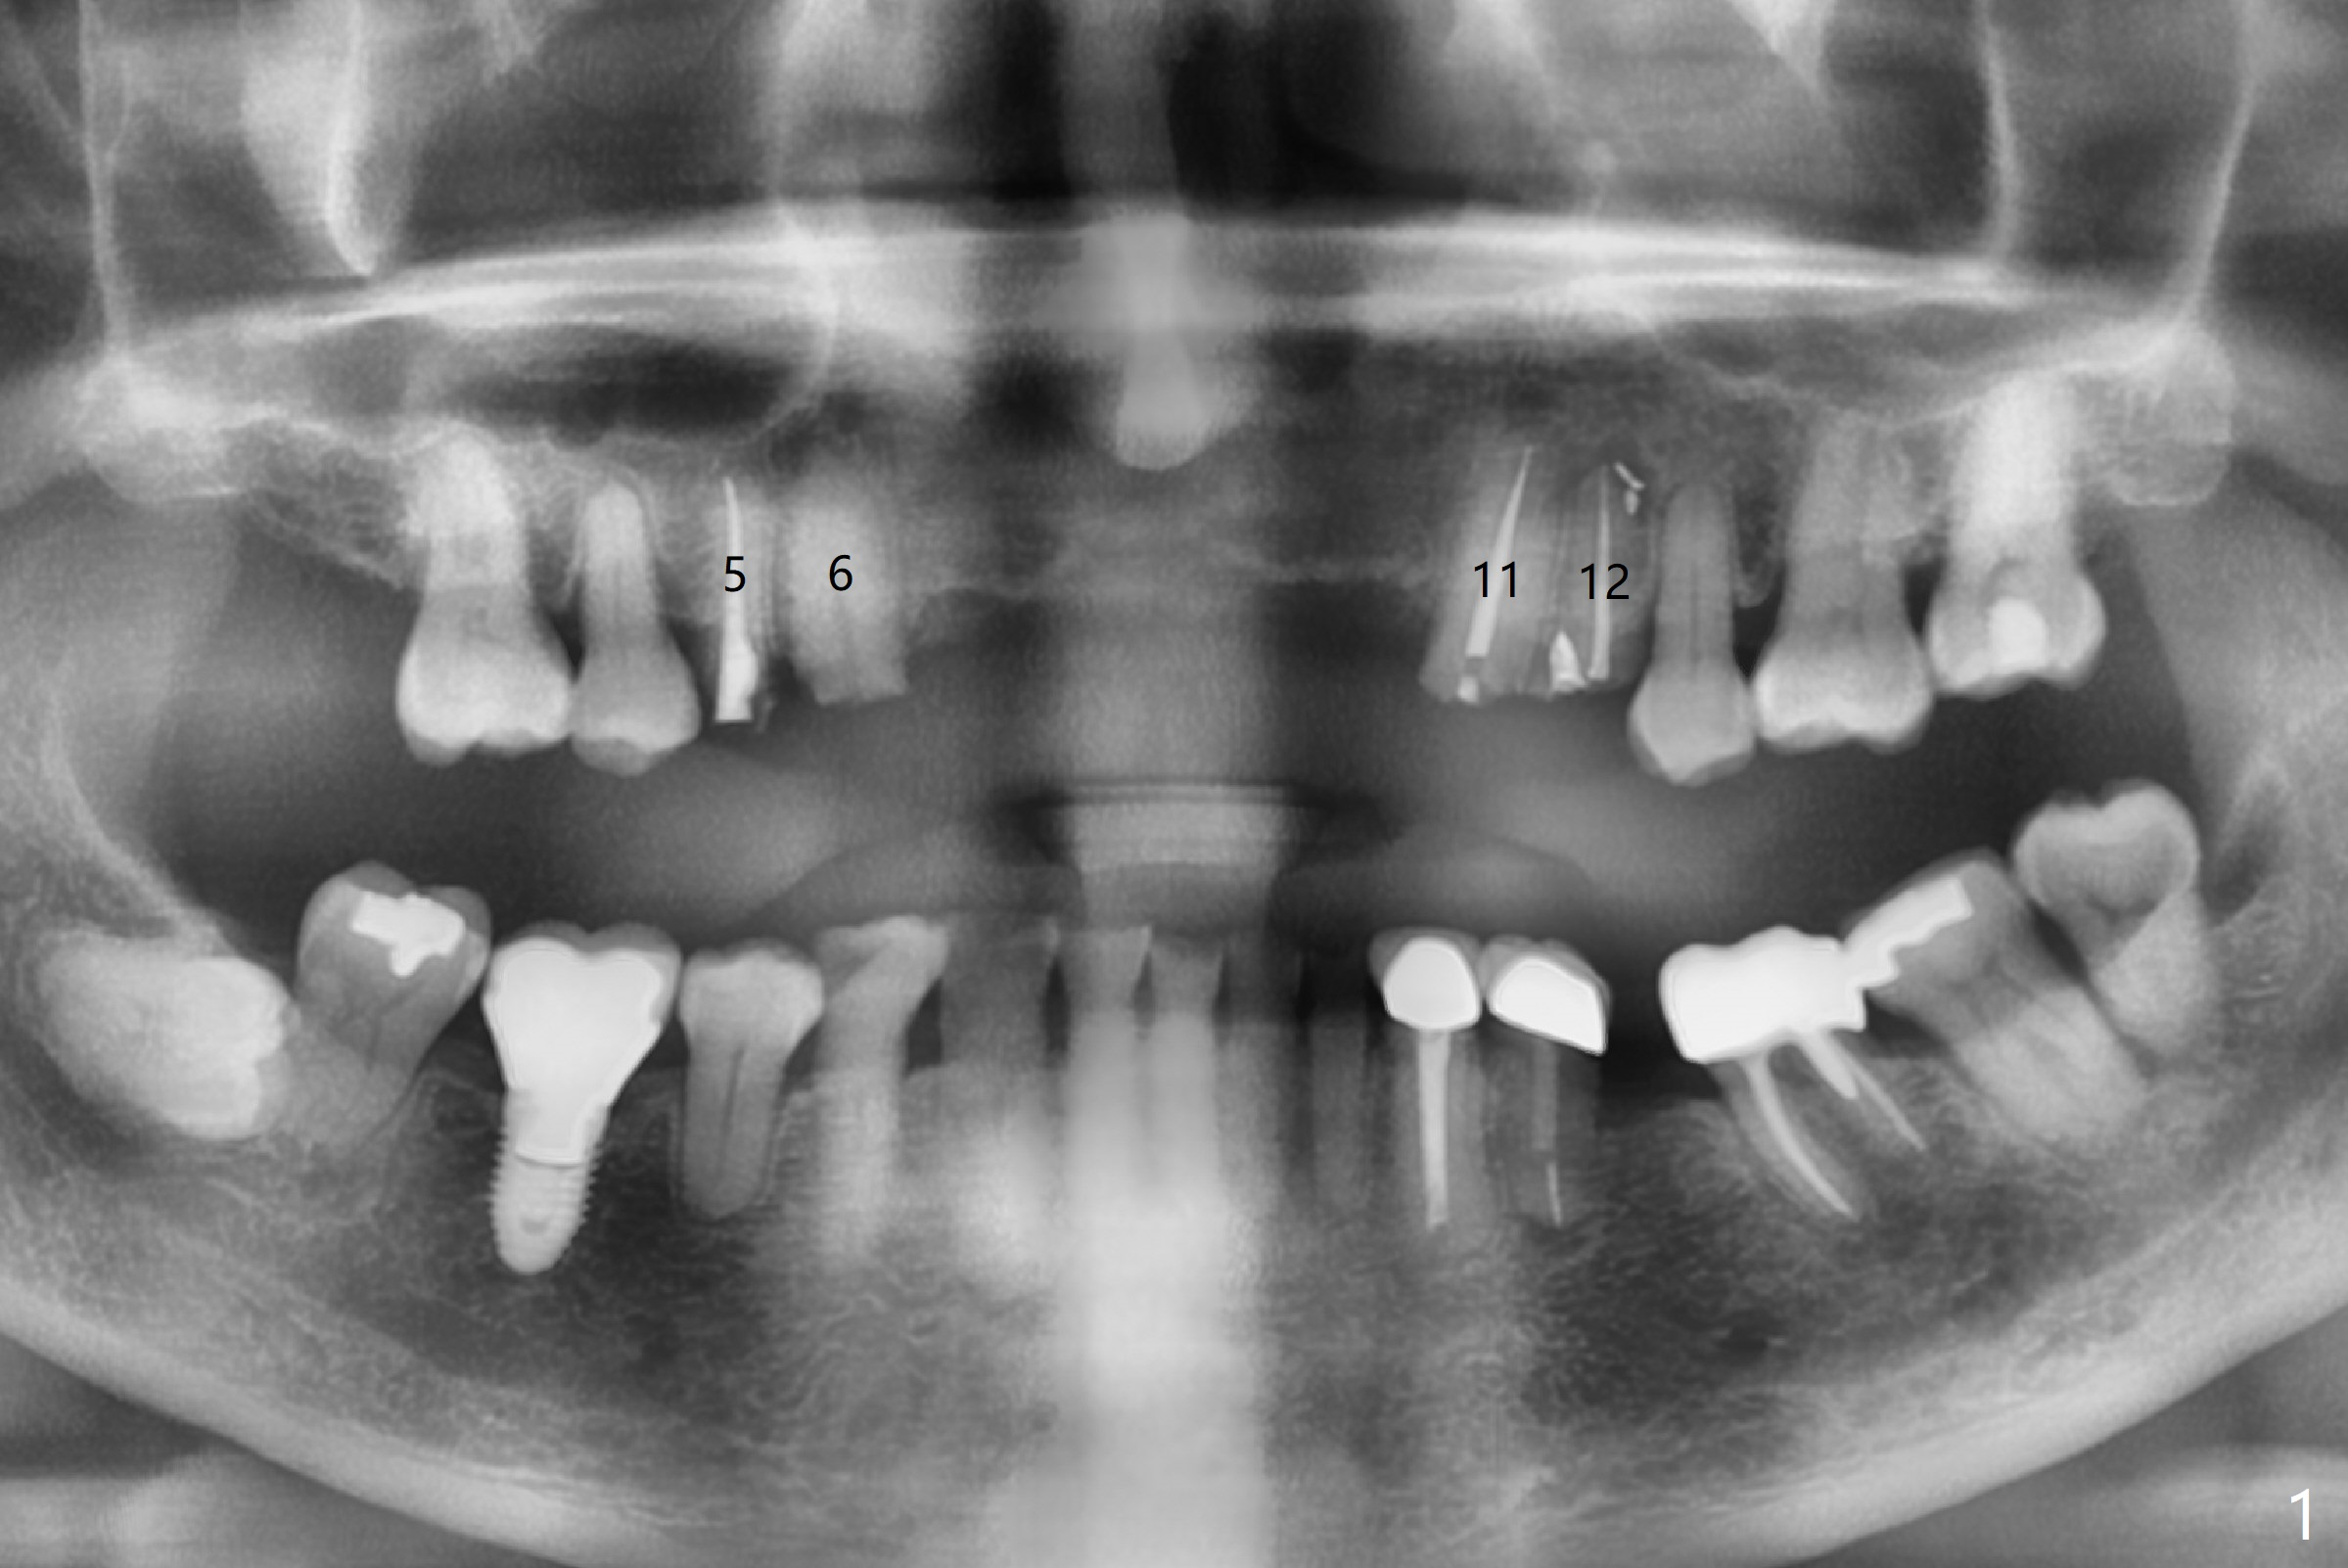

A 78-year-old man's 8 unit FPD dislodges (#5-12, Fig.1). Three of 4 abutments seem to be non-salvageable (#6,11,12 fractured equigingival, extraction, immediate implants). For restoration, implant will be placed at #8 and 9 as well. Implant FPDs will be fabricated at #6-8 and 9-11 (Fig.2) with #5 (with build up or prefabricated post) and 12 single unit crowns to better withstand deep overbite and overjet. After discussion with lab, a major change will be implants to be placed at #7 and 10 instead of #8 and 9 (narrow ridge). The implant at #7 will be a 1-piece (3 mm in diameter), whereas the rest 2-piece (3.5 mm). The abutment of IS 1-piece implant is 10 mm in length, while that of DIO's 5 mm. The former will be used if the vertical space is sufficient.